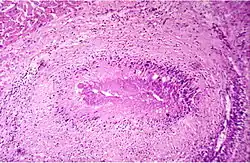

Die Gelenkzerstörung bei rheumatoider Arthritis ist vielmehr das Werk eines spezifischen onkologischen Prozesses, der sich schubweise aus der pluripotenten synovialen Zellmatrix entwickelt.[16][17] Die aggressiven homogenen Zellverbände, die in Knorpel und Knochen eindringen, bestehen aus dicht gelagerten großen polygonalen Zellen. Der große helle Zellkern enthält 1 bis 2 Nucleolen. Diese Zellen exprimieren eine Reihe hochpotenter proteolytischer Enzyme, die sie zur schnellen Zerstörung des Gelenks durch Degradierung von Knorpel und Knochen befähigen. Der gefäßfreie Prozess ist kurzlebig, die aggressiven Zellverbände kollabieren innerhalb weniger Tage und werden von Entzündungszellen und Makrophagen resorbiert. Entzündliche Faktoren sind am Zerstörungsprozess nicht beteiligt. Der Prozess hinterlässt jedoch den bekannten, oft fälschlich der Entzündung zugeschriebenen Pannus. Diese aggressive Phase kann sich am selben Gelenk wiederholen und den Zerstörungsprozess fortsetzen. Dieser für die rheumatoide Arthritis spezifische Prozess wurde vom Deutschen Krebsforschungszentrum als „tumor-like proliferation“ klassifiziert.

Eine weitere potenziell tödliche Komponente der rheumatoiden Arthritis ohne entzündliche Störung ist das akute Absterben von Geweben infolge einer lokalen Freisetzung von Kollagenasen. Es sind gelenkferne Prozesse, die durch eine zentrale Nekrose und eine dichte radiäre Zellpalisade gekennzeichnet sind. Sie zerstören gefäßarme, kollagene Strukturen. In Sehnen führen sie zur Sehnenruptur, im Auge befallen sie die Sklera, was zum Verlust des Auges führt. Sie können die Wandung von Arterien zerstören und damit zum Absterben von Gliedmaßen führen. Dies sind Prozesse, die sich der klinischen Beobachtung weitgehend entziehen und deswegen oftmals anderen Erkrankungen zugeschrieben werden (z. B. Herzinfarkt).[13]